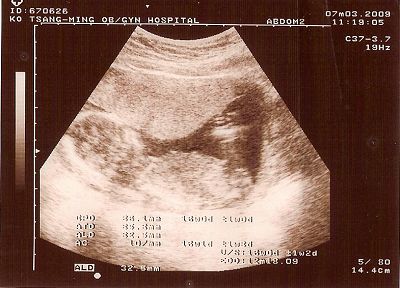

先照了超音波,說應該是女生

由柯醫生下針,另一個女醫生抽羊水

神奇的是,下針一點都沒感覺,抽羊水的過程有點酸酸的

大約一分鐘吧,抽針結束